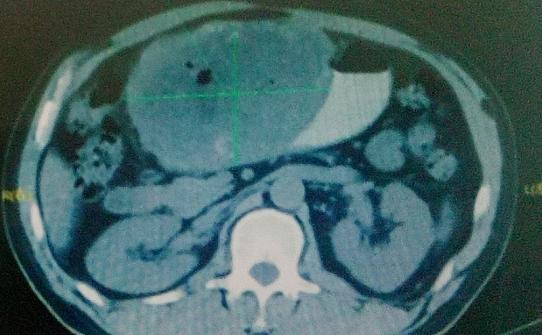

完善各项入院检查后,行缓释库治疗多次,于2015年10月1日复查腹部CT:肝左叶巨大肿块,肝肿瘤明显缩小,最大截面约13.5cmx 11.1cm。AFP下降至400.01ng/ml.治疗后体重增加10kg。